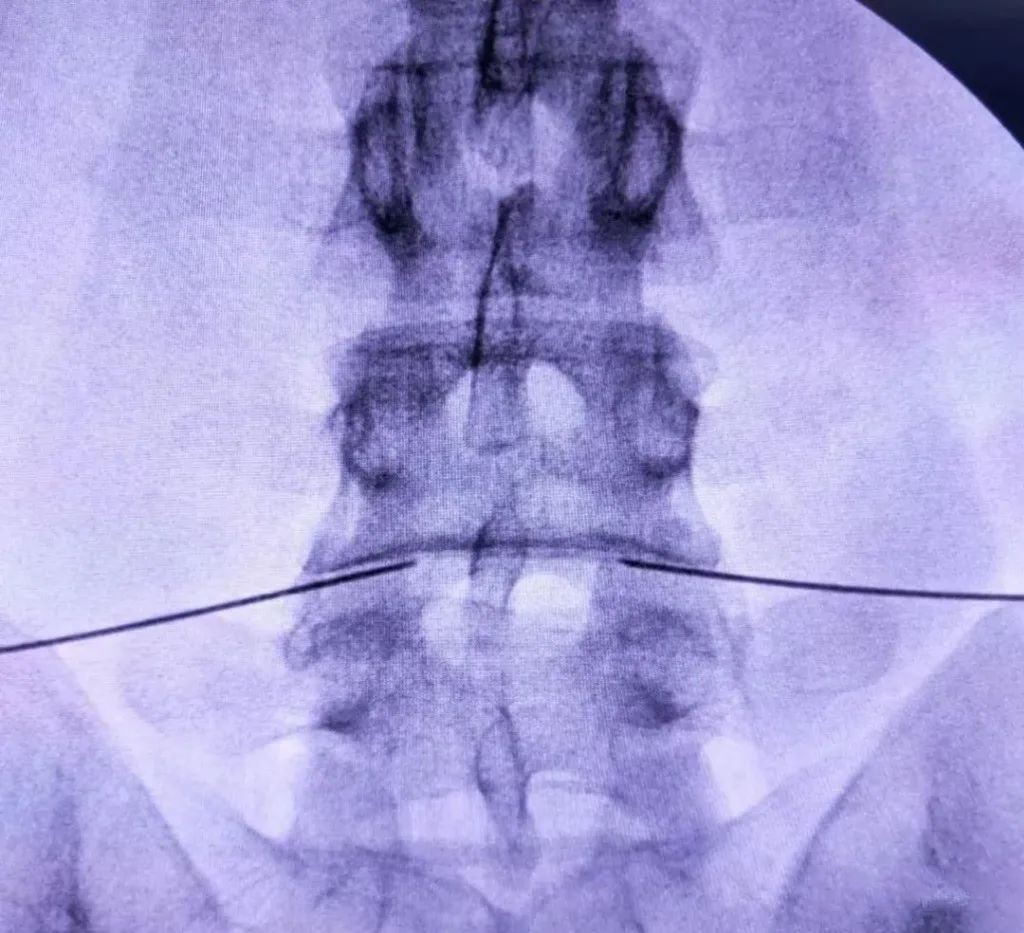

X线引导下L4-5椎间盘双侧射频针置入

正侧位示位置准确